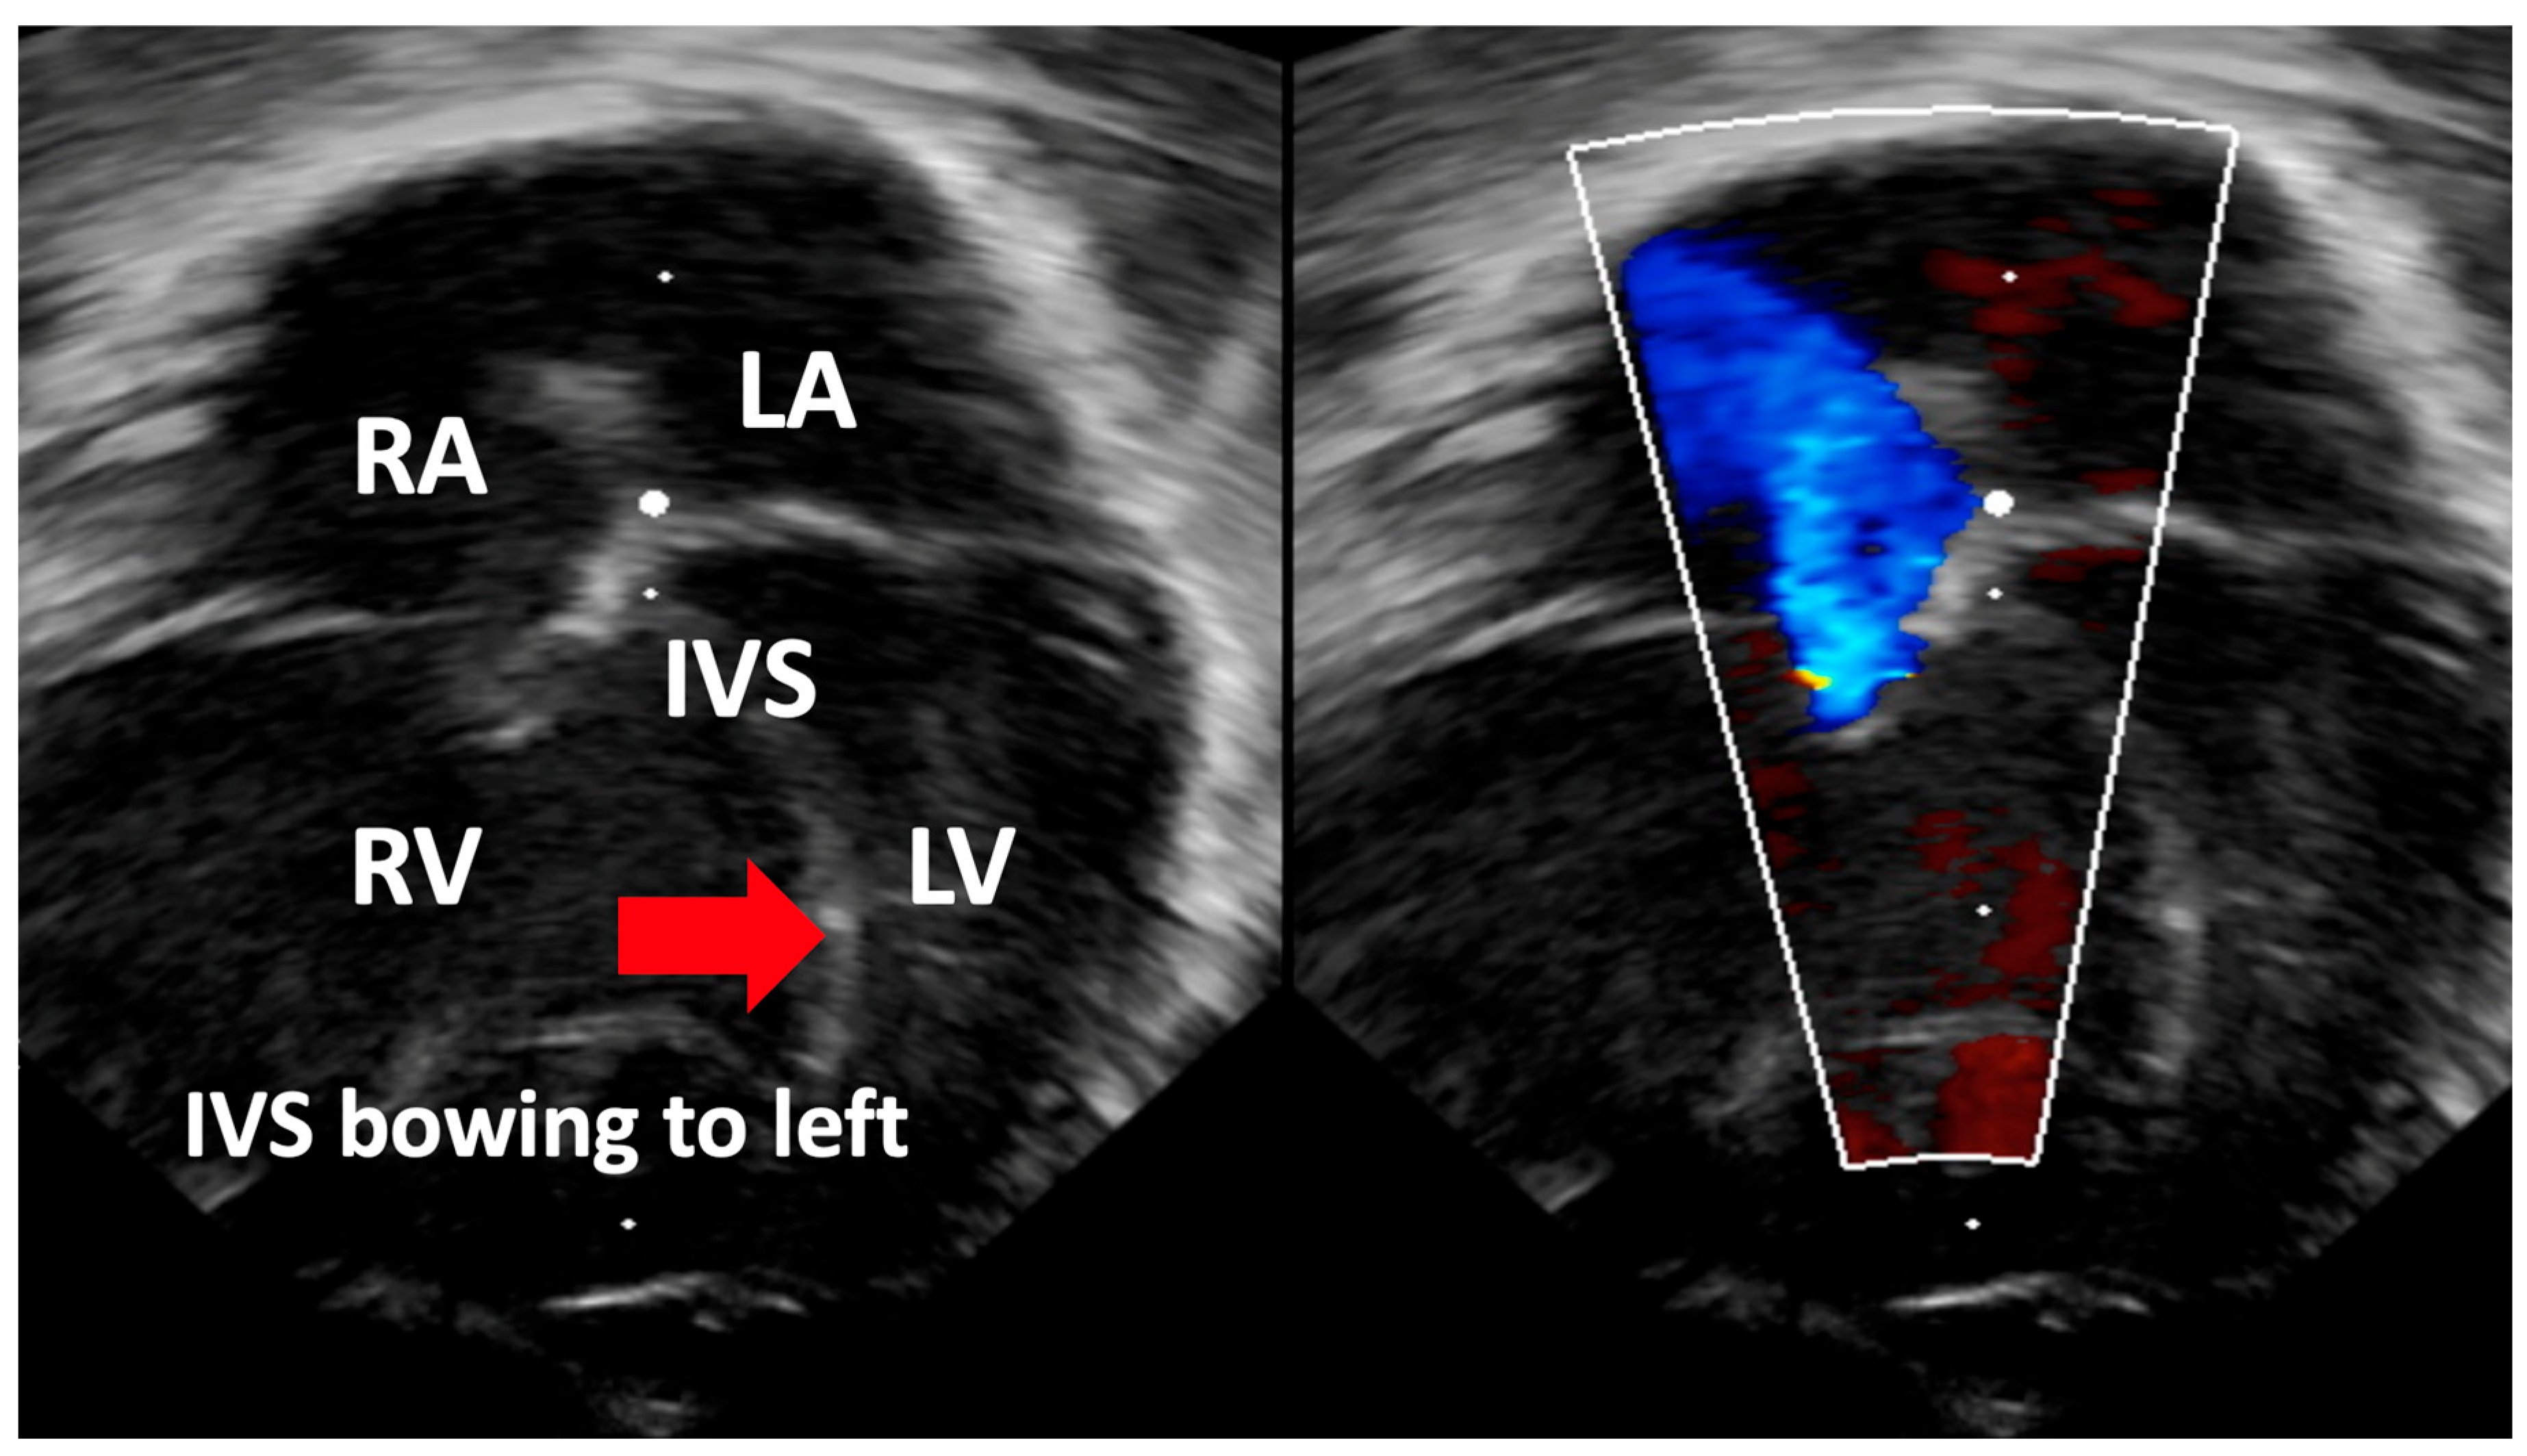

| Interventricular Septal (IVS) | Evaluation of interventricular septal flattening | Helps in estimating severity of PPHN, especially in absence of tricuspid regurgitation or PDA (Figure 4) O-shaped LV suggests normal or mildly increased pressure pulmonary artery pressure D-shaped LV with flattening of IVS indicates pulmonary artery pressure 50–100% of systemic pressure Crescent-shaped LV indicates pulmonary pressure > systemic pressure |

| Detection of Shunt | Identification and assessment of flow through the patent foramen ovale (PFO) and ductus arteriosus (PDA) | Indicates the presence and nature of pathological flow: left-to-right, bidirectional (often in moderate PPHN), or right-to-left (in very severe PPHN) |